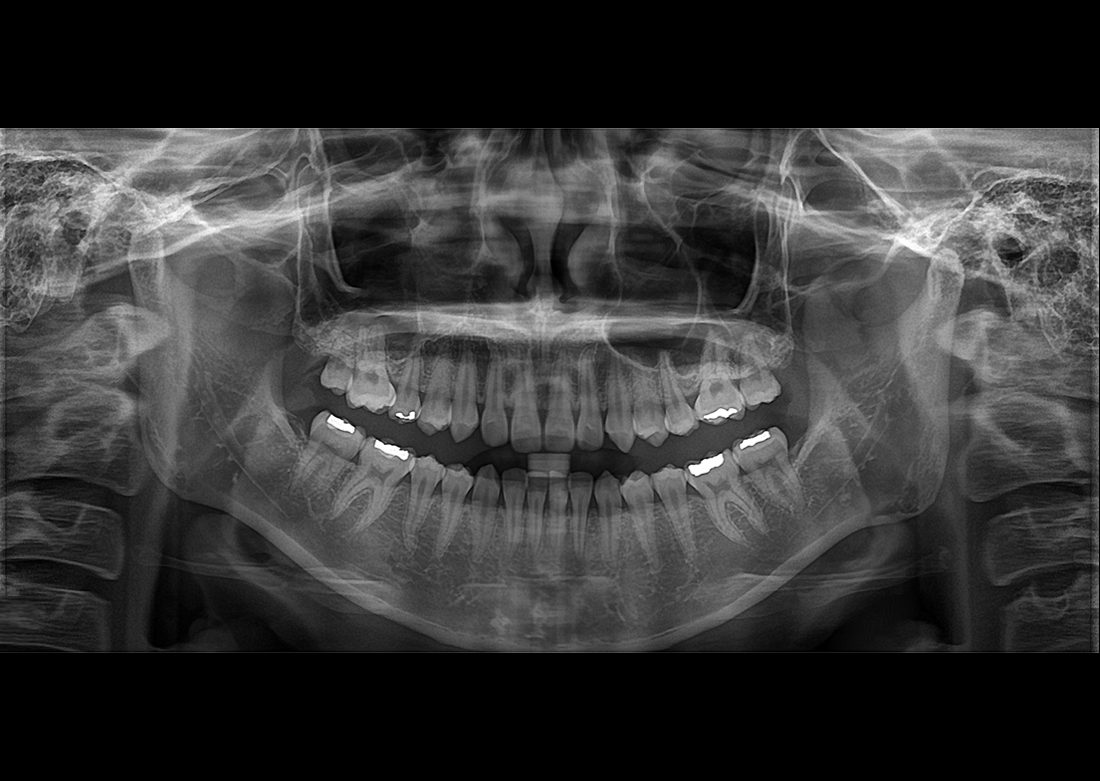

KLİNİK FOTOĞRAFLAR

Yılların tecrübesi ve geliştirdiği know-how teknolojileri ile muhteşem teşhis görüntüleri yaratmak Genoray firmasının herzaman gururu olmuştur..